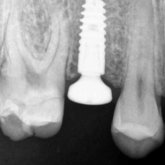

He received his Diploma in Implantology in 2016 from the University of Pretoria, which he passed with Distinction. He is also a member of the International Team for Implantology (ITI), which is based in Switzerland and offers members access to the latest research and cutting-edge techniques.